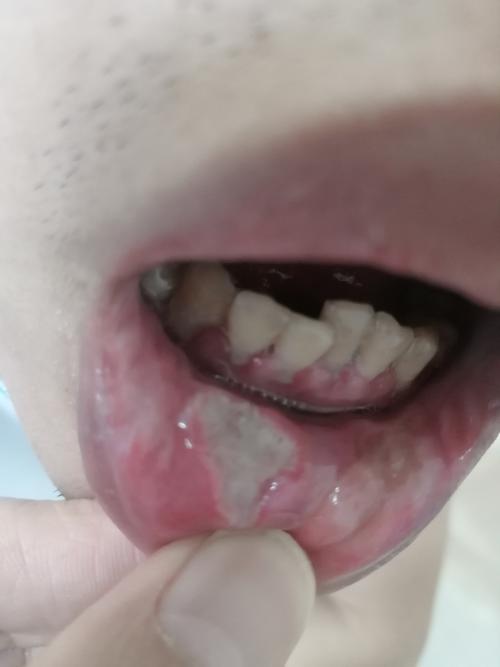

口腔溃疡频发,是咬破嘴惹的祸吗?

您遇到的情况可以概括为“创伤性口腔溃疡”,它的发生路径通常是:

- 诱因(咬破):由于各种原因,您在不经意间咬到了自己的口腔内壁、脸颊内侧或舌头。

- 伤口形成:牙齿的压迫和摩擦在口腔黏膜上造成了一个小破口或撕裂伤。

- 感染与炎症:我们的口腔中充满了细菌,当黏膜屏障被破坏后,细菌很容易侵入伤口,引发局部的炎症反应,身体自身的免疫系统也会识别这个“入侵点”,派出免疫细胞进行“修复工作”,这个过程也会导致局部红肿、疼痛,形成溃疡。

- 溃疡形成:炎症反应导致黏膜表层坏死、脱落,形成一个凹陷的、疼痛的溃疡面。

- 再次咬到:溃疡形成后,由于疼痛和肿胀,您在说话、吃饭时可能会更加小心翼翼,反而改变了咀嚼习惯,导致舌头或脸颊不自觉地去摩擦或再次咬到那个敏感的溃疡区域,从而延长了愈合时间,甚至加重病情。